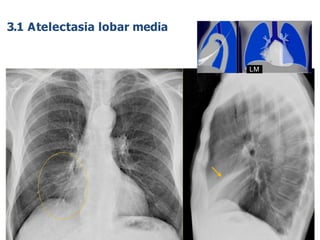

LM

3.1 Atelectasia lobar media

Causas:

• Carcinoma bronquial (fumadores)

• Tapón mucoso en pacientes con ventilación mecánica o reactividad bronquial

(aspegilosis alérgica)

• Sonda endotraqueal mal posicionada.

• Cuerpo extraño.

A veces las AL producen únicamente discreta pérdida de volumen debido a

la hiperinsulflación compensatoria de otras partes del pulmón

3.1 Atelectasias lobares (AL)